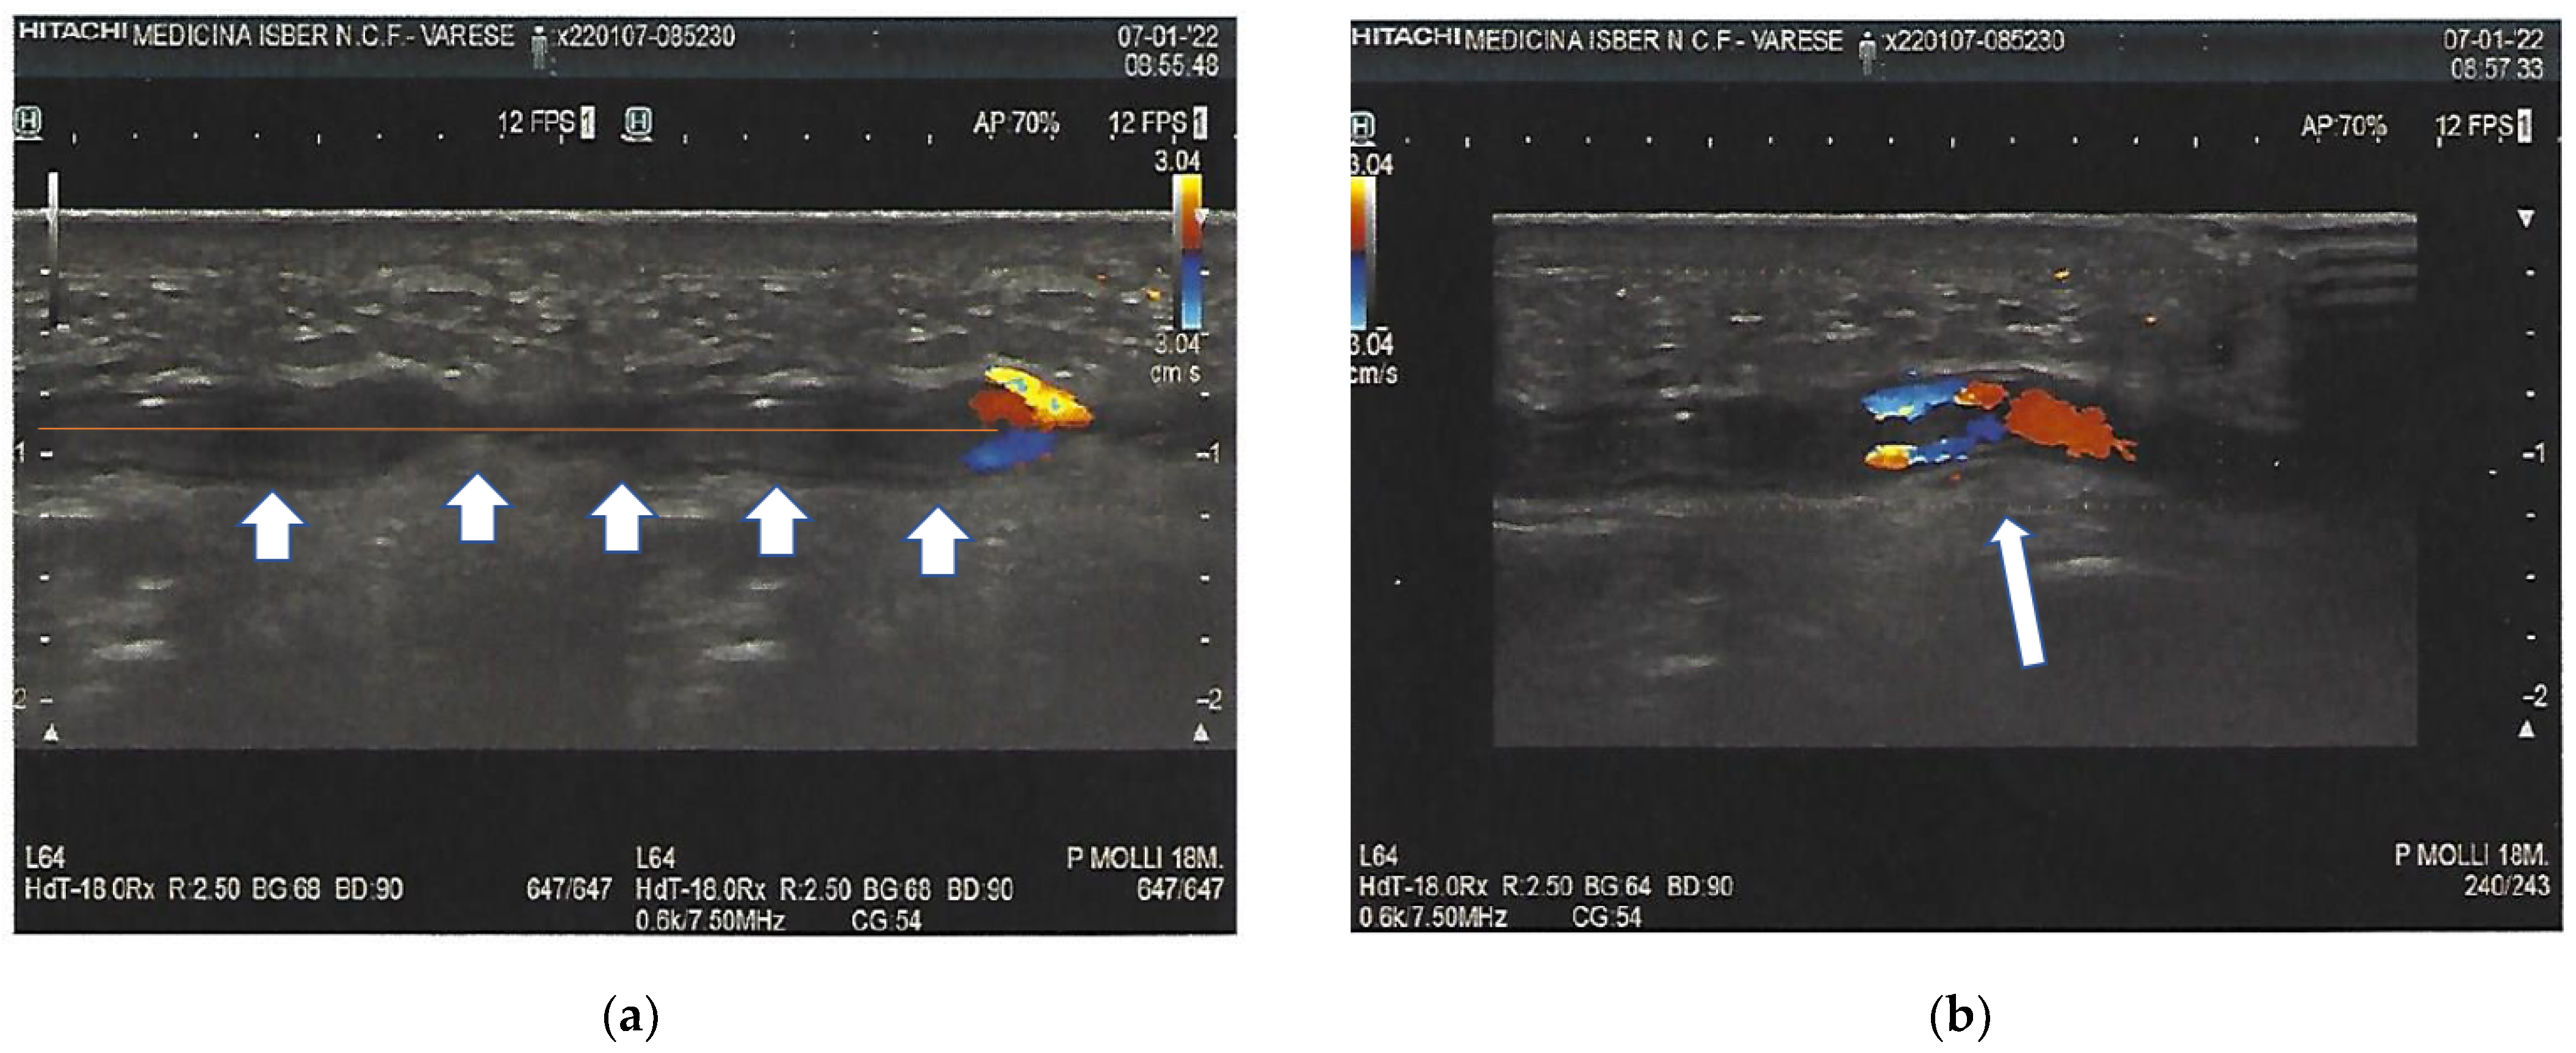

2. Case Presentation

3. Investigations

6. Outcome and Follow-Up